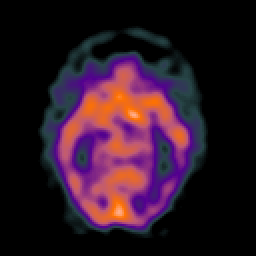

SPECT TC Study #1 -- Slice #23

[Home][Help][Clinical][Tour 1][Tour 2][Tour 3] Slice 23